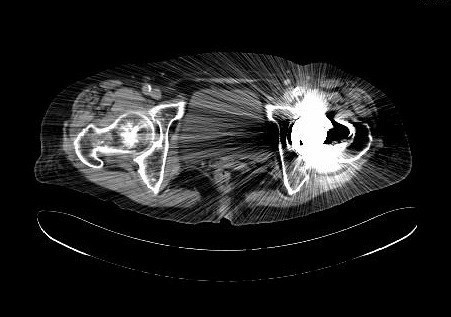

查体:专科:左髋部后外侧陈旧手术瘢痕,左髋关节前方压痛、无轴向叩击痛阴性,无大转子叩击痛,双下肢感觉及血运均正常。双下肢肌力V级。动量:右髋内外旋诱发疼痛,屈曲90度疼痛。外旋明显滚动试验阴性,左髋4字试验阳性。双下肢等长。左髋关节屈90°,伸0°,外展40°,内收20°,内旋30°外旋10°。右髋关节屈120°,伸直0°,外展40°,内收20°,内旋30°外旋30°。 辅助检查:2010-12-08 ESR 6.0mm/h,2011-01-04外院CRP8.5mg/l(参考范围0-10mg/l)X线示左双动股骨头置换术后,假体松动、下沉,髓腔内可见骨水泥影。近端干骺端骨质明显缺损。髓腔内侧皮质形态不规则。

诊断:左双动股骨头置换术后假体松动、下沉、股骨骨缺损(PaproskyII型) 治疗:患者在全麻下左双动股骨头假体取出+同种异体骨植骨+左全髋关节翻修术,术后予以抗炎(二联)+抗凝+镇痛+护胃+补液等治疗,并予以抗骨质疏松药物